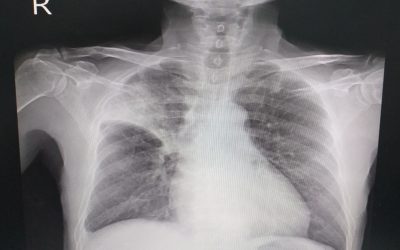

Atelektaza se odnosi na respiratorni poremećaj u kojem alveole u plućima kolabiraju, što dovodi do potpunog ili djelomičnog kolapsa pluća. Zatvaranjem dišnih struktura dolazi do ozbiljnog oštećenja tj